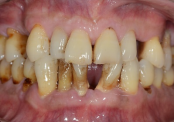

牙龈肿痛溢脓                            牙齿松动、移位、脱落